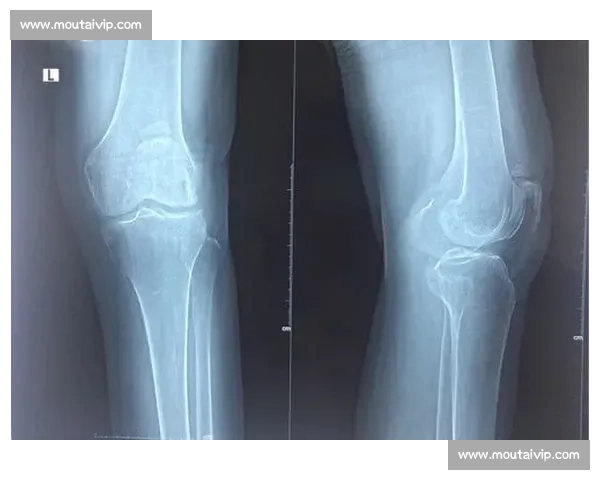

但膝盖的旧伤阴影始终挥之不去。2023 年 11 月的欧洲杯预选赛中,加维在一次停球变向时遭遇右膝十字韧带完全撕裂 + 外侧半月板损伤,当时他在场上痛哭的场景让无数球迷心碎。那次重伤导致他缺席了 349 天,错过了西班牙队的欧洲杯夺冠之旅,直到 2024 年 10 月才重新进入比赛大名单。如今可能出现的新问题恰好发生在同一侧膝盖,不禁让人担忧是否存在关联性损伤。医学资料显示,关节镜手术作为微创治疗手段,虽比传统开放手术恢复更快,但具体康复周期仍取决于损伤程度 —— 简单修复需 2 - 4 周,而复杂重建则可能需要 8 - 12 周甚至更久。对于加维这样依赖爆发力和变向能力的中场球员,膝关节稳定性至关重要,任何修复手术都需要极其精密的术后康复计划。